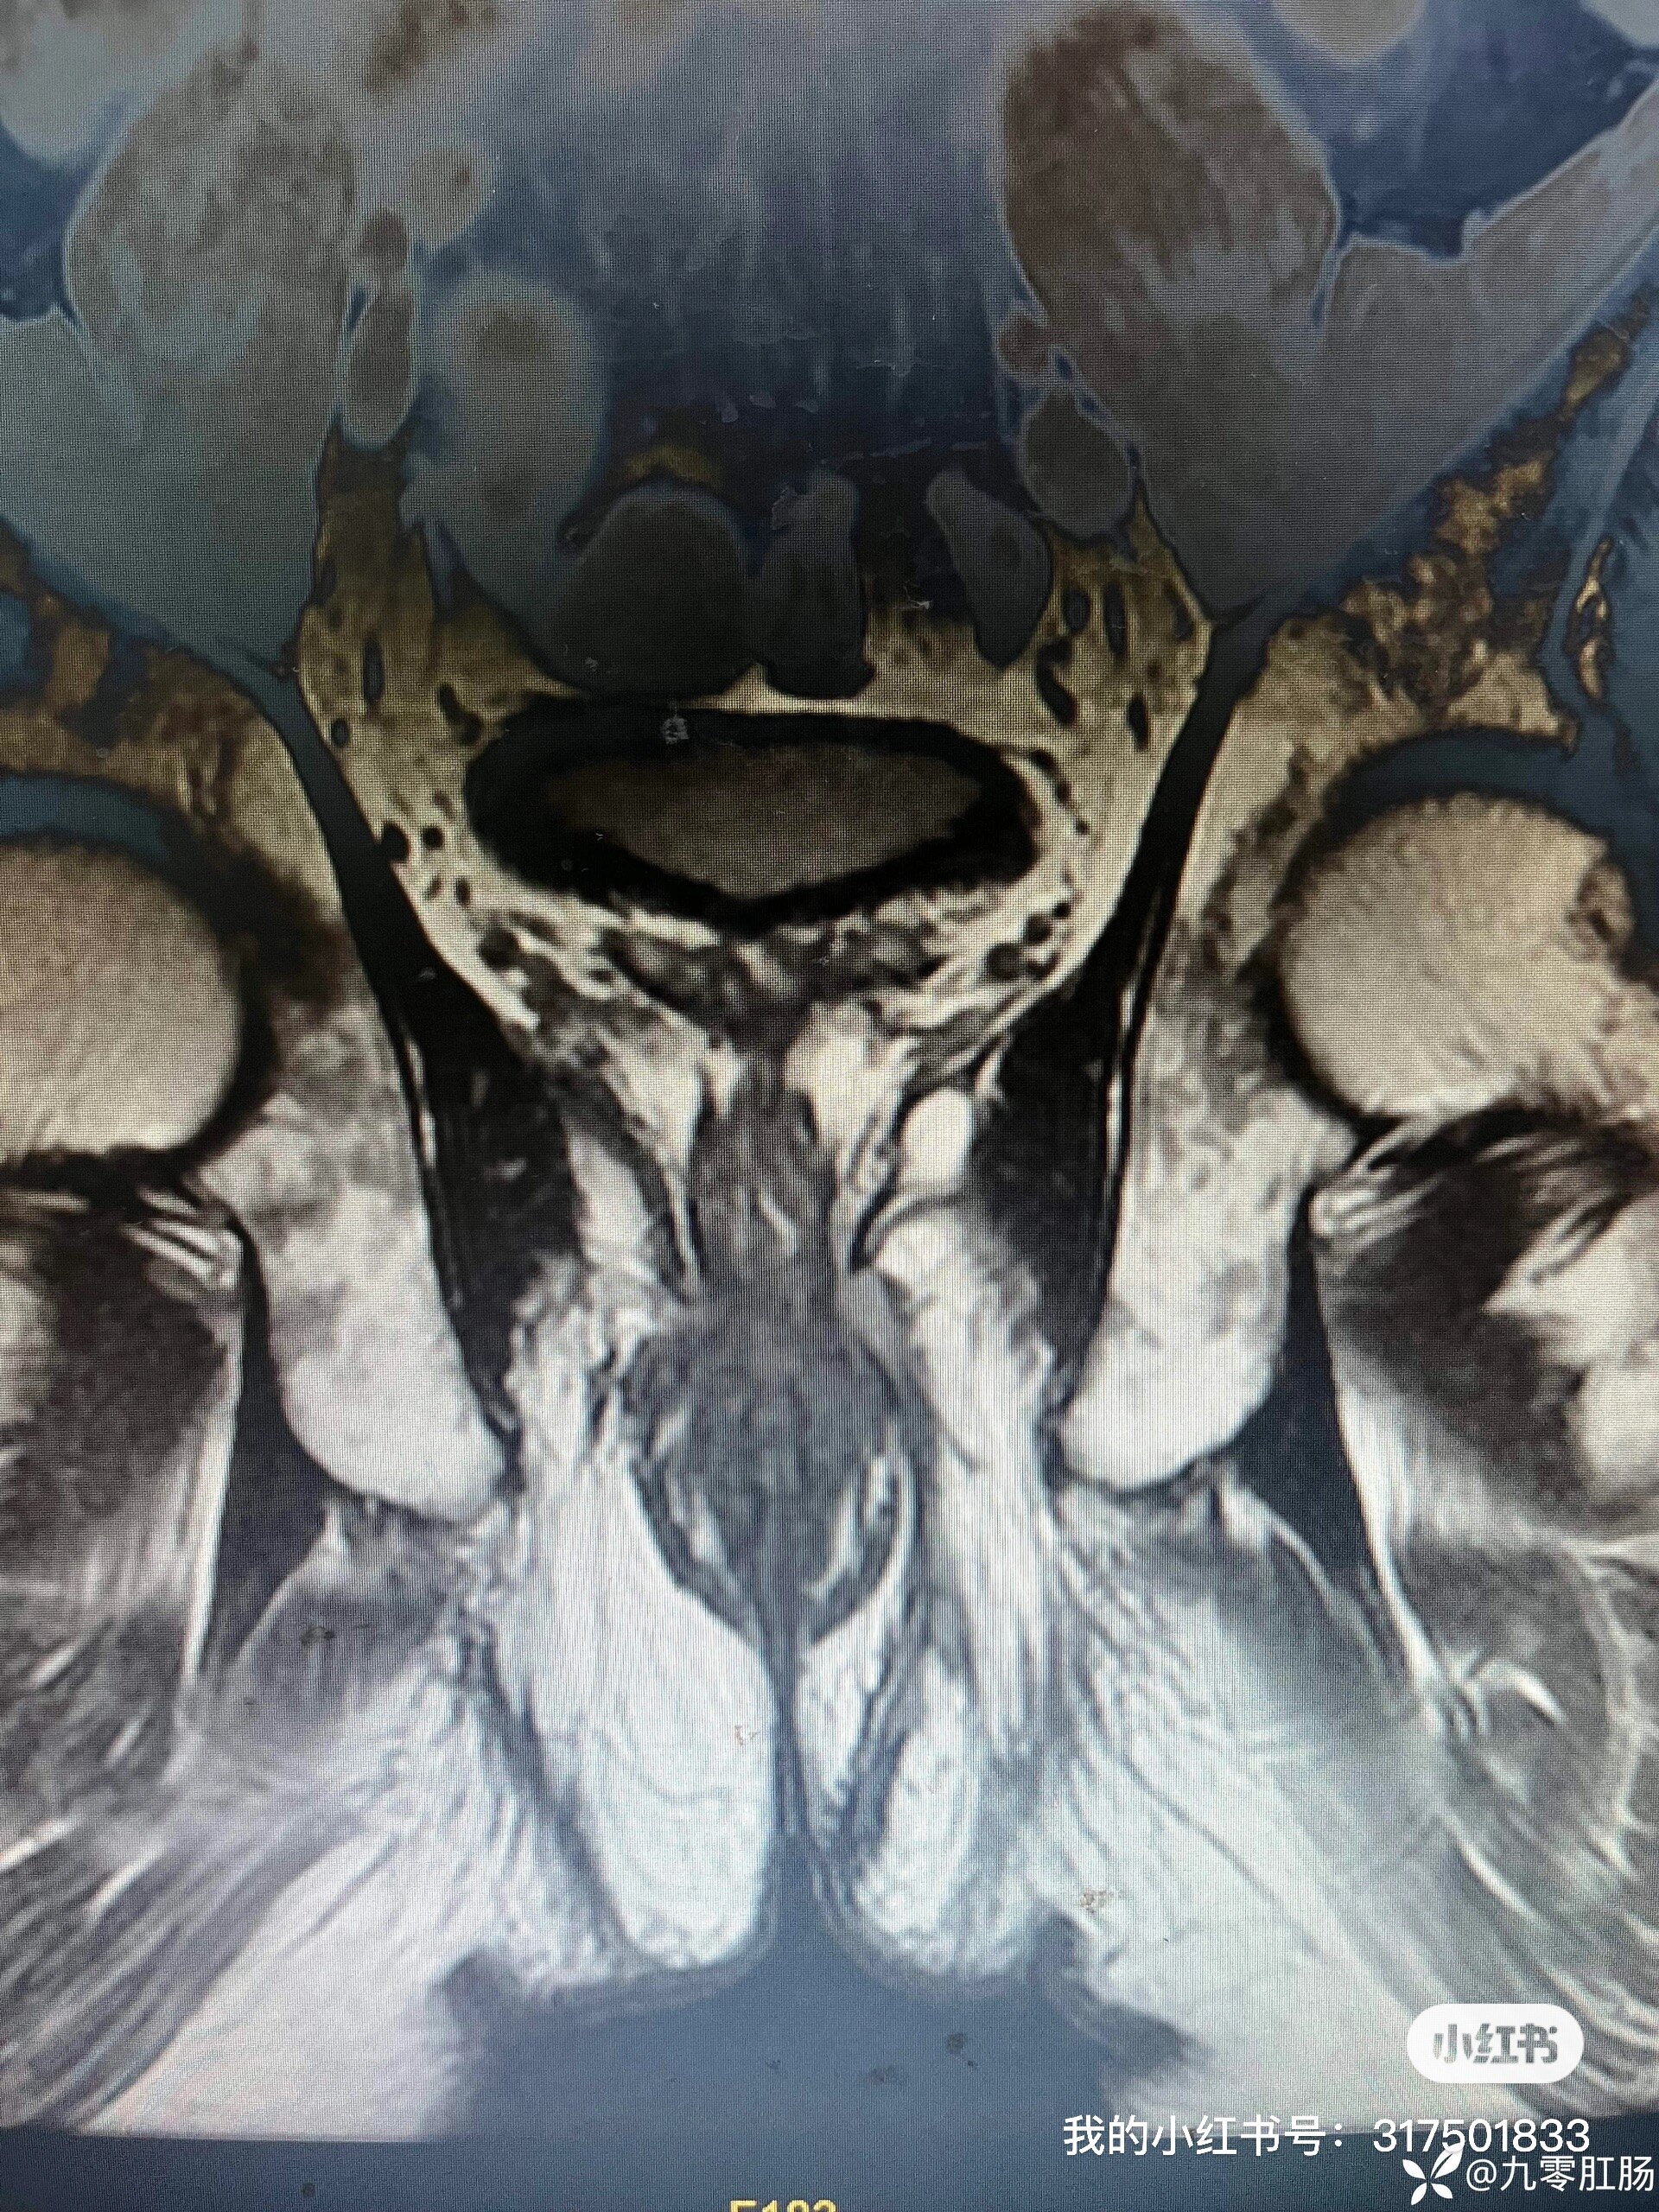

治療前患者男,50歲,反復(fù)肛門腫痛10年,4個月前在外院行肛瘺手術(shù)治療,術(shù)后癥狀反復(fù),伴肛旁流膿水。治療中術(shù)前磁共振檢查提示左側(cè)括約肌上瘺(內(nèi)口位于12點。沿12點肌間蔓延至DPIS間隙,向后突破部分恥骨直腸肌,突破左側(cè)恥骨直腸肌,向下經(jīng)左側(cè)坐骨直腸間隙至左側(cè)肛周皮膚)治療后治療后即刻對于復(fù)雜性肛瘺,術(shù)前必須明確診斷,強烈建議磁共振檢查!??!千萬不要按照傳統(tǒng)方法,術(shù)中“亂切亂捅”,治療過度不僅造成肛門不可逆損傷(門診見到太多這樣的患者了,很無奈?。?,而且加重術(shù)后疼痛。治療不徹底又會造成像該例患者高位感染間隙遺漏的情況。在肛門這塊寸土寸金的地方,本人始終堅持肛門功能的保護(hù)是治愈的前提?。?!這位患者采用TROPIS+Parks松弛掛線,不僅最大限度降低了損傷,保護(hù)了肛門功能,同時術(shù)后疼痛非常?。ɑ颊哂H訴)。一切源于精準(zhǔn)治療?。。?/p>